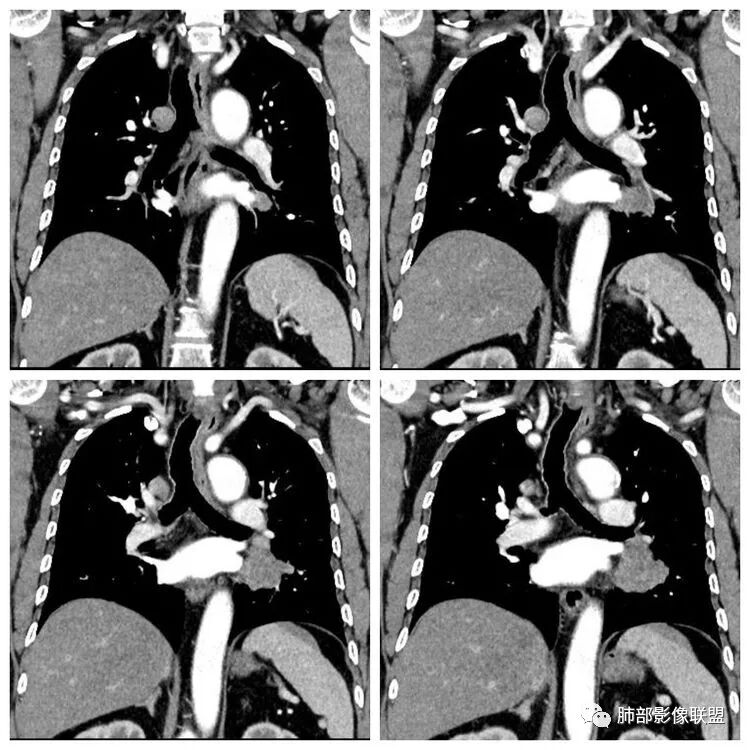

患者,男 ,66岁, “左肺占位”收住院。CEA   5.23 轻度增高

平扫 动脉期 静脉期  40HU、48HU、57HU

患者老年男性,“左肺占位”收入住院。查CEA轻度升高。胸部CT:左肺肺门占位并左肺下叶阻塞性,远端肺组织膨胀不全,增强可见轻度强化,内似见低密度灶。双肺多发类圆形结节,以左肺上叶尖后段为大,内可见部分钙化,边缘光滑、清楚。综合考虑恶性病变,鳞癌并转移可能大,鉴别腺癌、结核。

胸CT:左下叶内前基底段肿块,支气管堵塞,强化弱,延迟强化,两肺多处结节,右上肺门淋巴结大。常规考虑:肺癌可能 ,肺内小结节,转移?鉴别:错构瘤,TB等。

左肺下叶占位,左肺下叶前内支气管阻塞可疑(缺乏薄层),病灶有膨胀性,远端较内侧细,增强病灶强化不明显——乏血供病灶,病灶沿支气管生长,考虑恶性病变,左肺上叶可见小结节病灶,边缘光滑清晰,考虑转移瘤,综上所述考虑恶性病变,左肺下叶小细胞类癌可能,左肺上叶转移。

1.定位:左肺块影同时累及下舌段及下叶内基底段且相互延续。病灶跨叶,或存在叶裂发育异常,或者说就是病灶的肺门蔓延。

2.病灶前上部分与舌段支气管相关且形成阻塞。

4.增强扫描左肺门区块影轻度强化,强化程度轻于舌段周围不张肺组织。